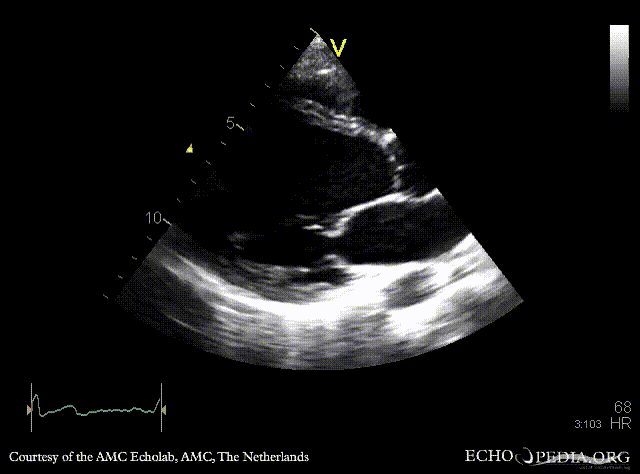

Dilated cardiomyopathy

PLAX: dilated poor left ventricle in patient who receives chemotherapy PSAX: dilated poor left ventricle